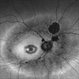

- Left fundus photograph of a 50-year-old female patient with spontaneous retinal reattachment five years after visual loss.